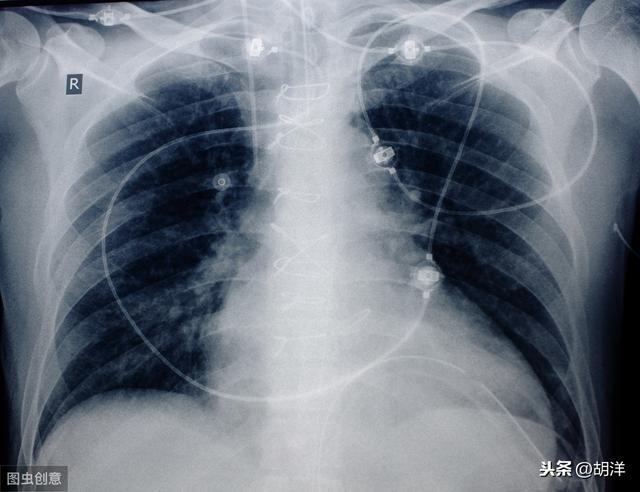

この患者はまだ39歳で、胸のつかえと息切れがあり、右肺の腺がんと診断され、多量の胸水が貯留し、右肺全体の機能が失われていた。このような重篤な状態は高齢者にやや多く、放置すればすぐに呼吸不全に陥る。幸いなことに、彼女は標的治療に感受性があり、胸水をコントロールしながら3年以上腫瘍と共存している。